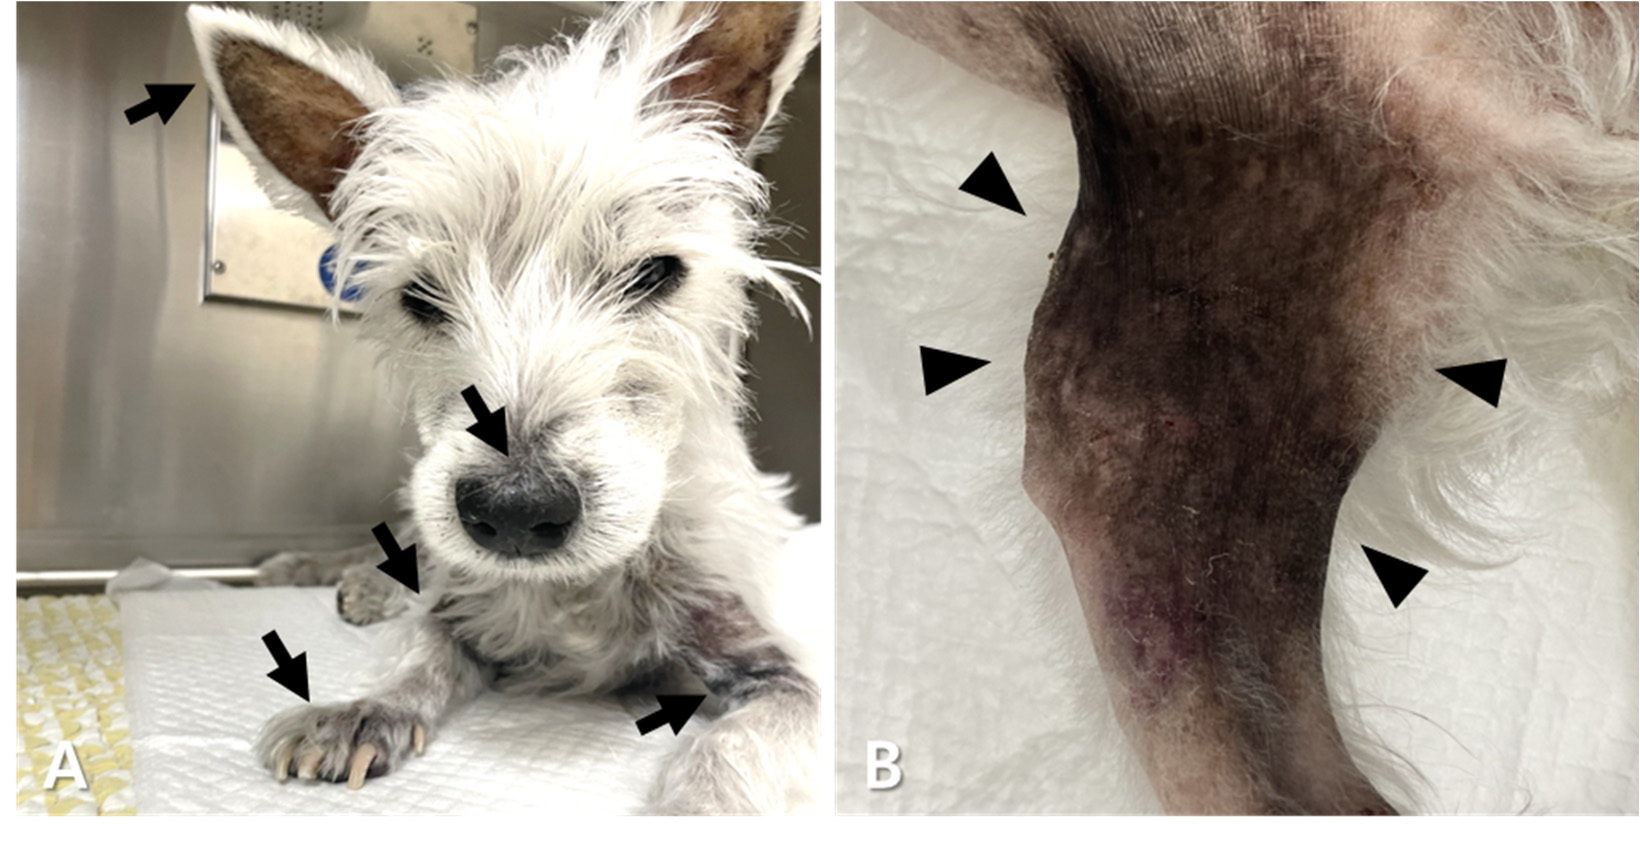

第339天,开始使用索拉非尼(3 mg/kg,口服,q24h)。即使与硼替佐米联合使用,在20天后仍未观察到显著改善。索拉非尼和硼替佐米的联合治疗持续了33天。尽管观察到球蛋白短暂下降,但随后出现反弹性高球蛋白血症、贫血、血小板减少症以及皮肤症状(脱毛、色素沉着和多处皮疹)(下图)。尿液分析显示与并发尿路感染相关的血尿,还观察到因结肠炎导致的便血。

↑ 在耳廓、口吻部、颈部、腋窝区域和前肢观察到脱毛、皮疹和色素沉着(A;箭头),在腹股沟区域和后肢也观察到这些症状(B;箭头)。